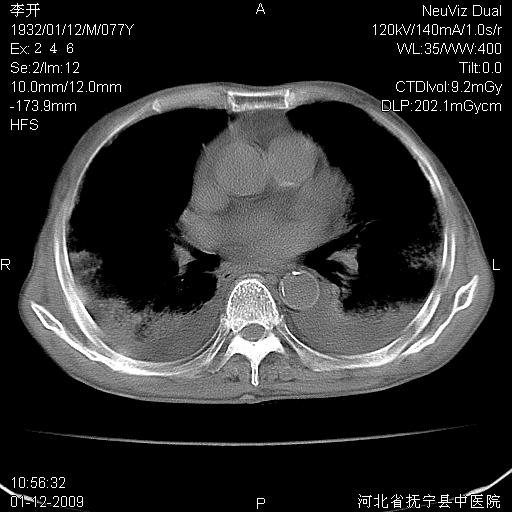

以下是引用黑白光影在2009-1-19 16:49:00的发言:[br]心衰肺水肿;心包、胸腔积液;冠脉钙化;肺部感染。